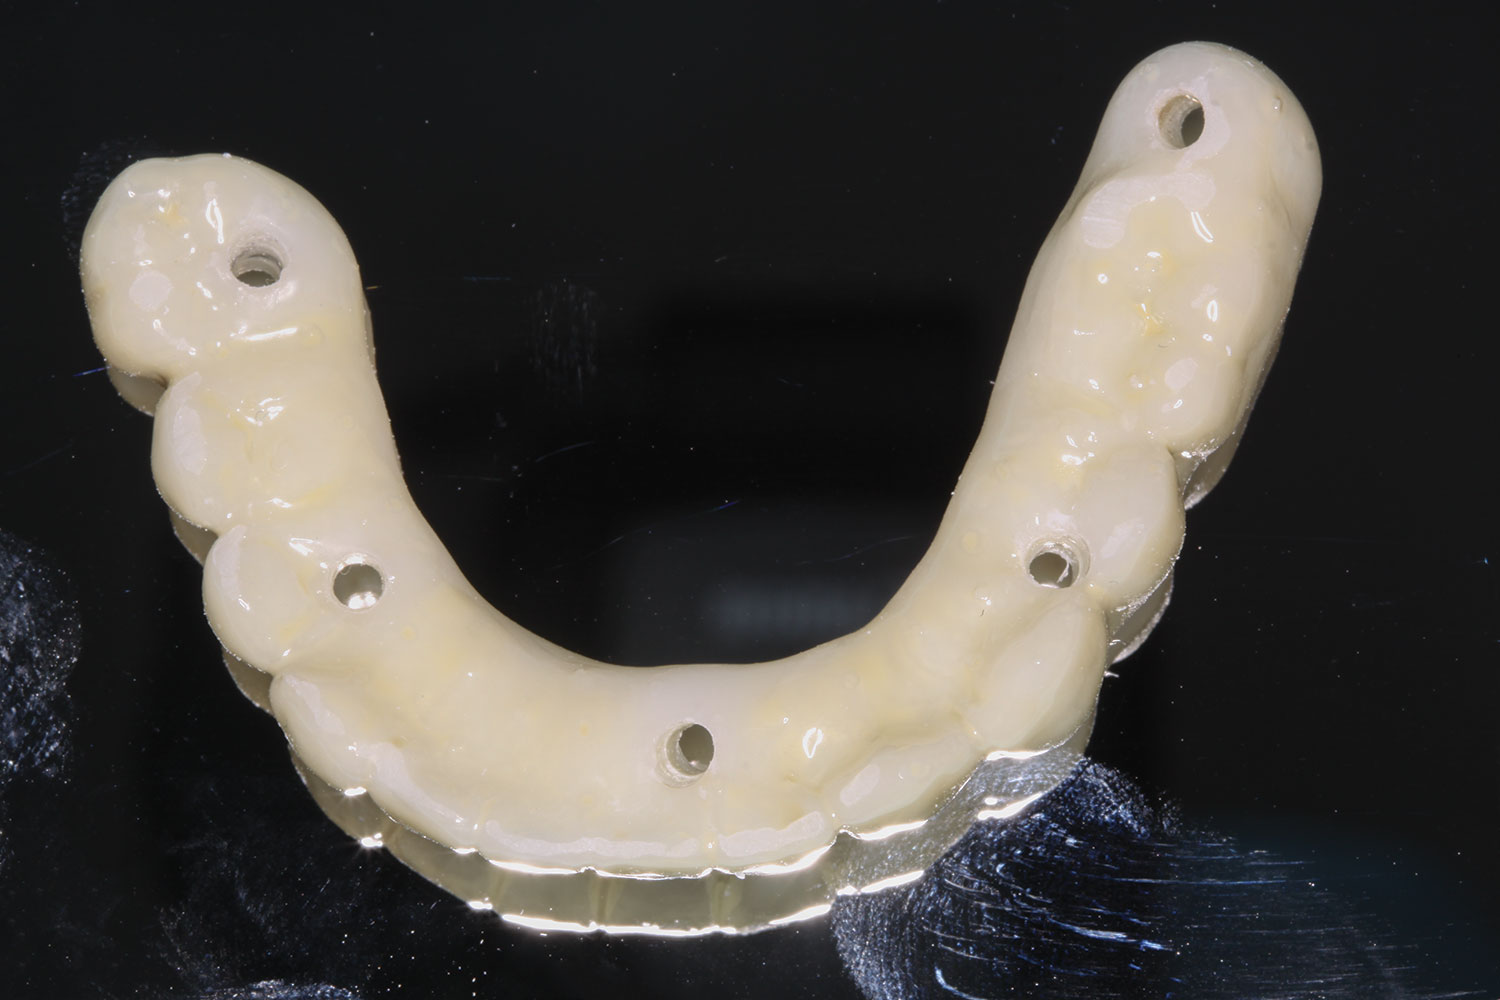

Fig 31. Mandibular provisional prosthesis printed demonstrating screw-access holes in prosthetically correct positions.

Figure 31

At the next visit, the patient was anesthetized with xylocaine with 1:100,000 epinephrine. Teeth Nos. 22, 27, and 28 were retained and all other mandibular teeth were extracted. Immediate implants were placed in prosthetically correct positions and multi-unit abutments were torqued to 30 Ncm. This was followed by insertion of screw-retained scan gauges in positions Nos. 18, 24, and 30.

At the completion of surgery for the mandibular arch, teeth Nos. 17, 21 through 24, and 27 through 30 had been carefully extracted. Immediate implants with multi-unit abutments were placed in sites Nos. 21, 24, 28, and 30, and an additional implant with a multi-unit abutment was placed in site No. 18. All multi-unit abutments were torqued to 30 Ncm. In the maxillary arch, at the completion of surgery, teeth Nos. 2 through 15 had been carefully extracted. Immediate implants with multi-unit abutments were placed in sites Nos. 4, 6, 8, 11, and 13, and all multi-unit abutments were torqued to 30 Ncm.